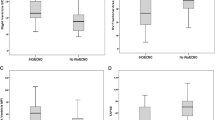

Magnetic resonance spectroscopy

There was no difference between animals that received epinephrine and placebo in Lac/NAA ratio measured in fCTX, oCTX, and Thal (Fig. 3). In WM, we were unable to detect lactate peaks in 3/6 animals resuscitated with epinephrine and 3/3 animals resuscitated with placebo. We found no difference between groups in NAA/Cr ratio measured in fCTX, oCTX, Thal, or WM (Fig. 3).

In total, 1/6 animals resuscitated with epinephrine and 1/3 animals resuscitated with placebo had severe MRS/MRI abnormality.

Magnetic resonance imaging

Cerebral edema quantified by DWI was similar in animals resuscitated with epinephrine vs placebo (Fig. 4). MRI-BOLD showed no difference in cerebral oxygenation between the two groups (Fig. 4).

Composite endpoint of death or severe brain MRS/MRI abnormality

We found no difference in the composite endpoint of death or severe brain MRS/MRI abnormality between animals resuscitated with epinephrine compared to placebo, RR = 0.7 (95% CI: 0.37–1.19). When including the only animal with missing MRS/MRI data in a sensitivity analysis assigning the piglet to a good or severe MRS/MRI outcome, the RR was 0.65 (95% CI: 0.34–1.12) and 0.74 (95% CI: 0.41–1.23), respectively.

We found no difference in brain MRS/MRI abnormality 6 h post ROSC based on Lac/NAA ratio, NAA/Cr ratio, DWI, or BOLD between animals resuscitated with epinephrine compared to placebo. The Lac/NAA ratio is known to increase during the secondary phase of energy failure between 6 and 24 h after cerebral hypoxia–ischemia.48 Thus, it is possible that we failed to capture the differences, i.e., both beneficial and adverse effects of epinephrine, due to the relatively short interval between CA and MRS. However, Zheng et al.49 showed that brain lactate levels peaked between 2 and 6 h following hypoxia–ischemia, and during our pilot studies, we performed both 6- and 12-h MRS/MRI examinations with no additional information gained. In addition, Tang et al.50 argue that pathophysiological changes after CA/hypoxia–ischemia, assessed by MRS/MRI, are more pronounced within the first 6 h after ROSC. Studies of adult CA have suggested that DWI-MRI can predict neurologic outcome as early as 3 h after ROSC.51,52 Our DWI results were in line with our MRS results that found no difference between the groups. This does not necessarily mean that a potential between-group difference would have settled at this timepoint. Accordingly, studies on long-term functional outcomes are needed. The majority of the animals had quite severe MRS/MRI findings; it is possible that we were unable to demonstrate any difference in MRS/MRI abnormality due to the severity of the insult. However, the model mimics a rare clinical condition where epinephrine is indicated with an a priori high risk of brain damage. A less severe insult would result in too many animals with spontaneous ROSC before drug administration.

We found no difference in the composite endpoint analysis of death or severe brain MRS/MRI abnormality. We decided not to use the clinical cut-off value of Lac/NAA > 0.39 to define severe brain MRS/MRI abnormality, as this value is extrapolated from human newborn studies and animal studies considerably different from our study with regards to timing of MRS; mean age = 5 days of life18 or even later,15 insult severity (not CA models), and MRS echo time (288 vs 135 ms).17,18,53 If our MRS results were equivalent to that of human infants, our findings would indicate severe brain damage with a high likelihood of adverse cognitive, motor, and language outcomes at 2 years of age.18 However, preclinical animal studies have shown that brain lactate measured by MRS decreases markedly while NAA increases between 6 and 72 h after a hypoxic–ischemic insult.49,50 The cut-off value to define severe brain damage should be higher when applied at 6 h compared to 72 h after the insult and beyond and when applied to CA models compared to HIE models. We therefore a priori chose to use a modified cut-off value of severe MRS/MRI abnormality.